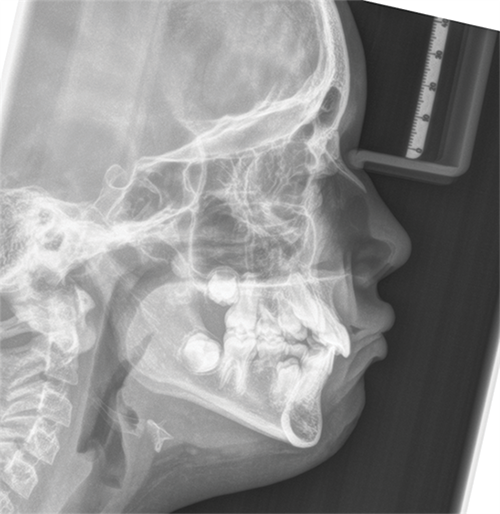

Another contributor suggested waiting until the 3s and 4s erupt, noting that doing so might also help stimulate the eruption of the 8s. Others agreed that timing would be key, and that allowing additional eruption before intervention could provide a clearer picture of space management and potential drift (Figs. 2-4). Still, some clinicians favored a more proactive approach, suggesting that early extraction of the E’s might encourage the 6s to drift mesially and simplify future treatment.

Fig. 3